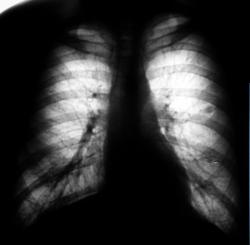

При расшифровке флюорограмм пациент "взят на контроль".

101.Rasshifrovka.JPG

Образование верхней доли левого легкого с дорожкой к корню, мне кажется может оказаться как периферическим раком ,так и туберкуломой.Надо начать с линейной томограммы. А нет ли вздутия переднего отрезка 3 ребра?

Этот дефект на всех снимках - это наше "факсимиле" - шутка. Дефект на экране, мы с ним уже смирились. Мы тоже подумали о периферическим раке и "дорожку" приняли к сведению. По поводу туберкулёза, как - то не подумали. Конечно, и о доброкачественной опухоли также вспомнили. Конечно, все "большие симпатии" в векторе периферического рака лёгкого.

И все таки похоже на туберкулому, мне кажется за год несколько уплотнилось образование, были более четкие,ровные контуры, а сейчас какбы чуть-чуть сжалось(или выдаю желаемое за действительное?). Просто у меня был очень похожий случай,только в нижней доле левого легкого за тенью сердца, с дорожкой к корню с лучистыми (как мне казалось)контурами образование чуть больше вашего,была уверена , что периферический рак, а больной сйчас в туб.диспансере лечит туберкулому.